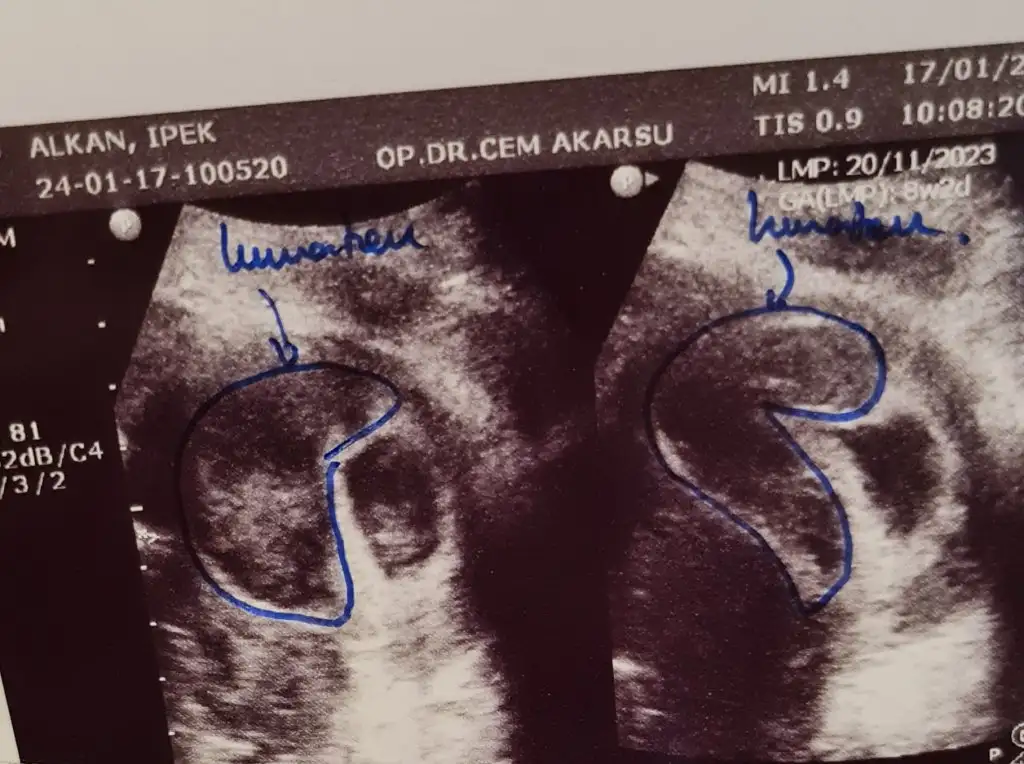

Bnde yunus hocamda tedavi gördüm ve dün transferim oldu .bnde memnun kaldım ilgisindenevet döner 27 aralıkta transferim gerçekleşti 6 ocak test günümdü ayın 4 ünde gece idrarda baktım negatifti ertesi gün kanda baktırdım pozitif çıktı.40 yaşındayım ilk denememiz 2 tane 4aa dondurulmuş embryo transferi yapıldı.Ultrasonda keseler görüldü şükür,ama kalp atışları için beta hcg min 3000 i geçmesini bekliyoruz.O da ayın 15 gibi olacakmış.

belirtilerim 6.günden sonra arttı ilaçlara yormuştum negatif sanıyordum şoktayız.1 kızım var 10 yaşında Allah nasip ederse ikizlerimizi bekliyoruz şimdi.

Öncelikle geçmiş olsun ama bak çok şükür bebeğin gelişimi, kesesi çok iyimiş canım. Sıkma canını dikkat et bol bol dua inşallah. Bide neden çoğalabilirmiş sordun mu? Sende gün aşırı kahverengi akıntı falan oluyor muydu?kizlar sabah gittik doktora bu sefer karindan bakti o yuzden aynalama oldu kan alani sagken solda gorundu resim eklicem ama hic azalma olmamis aksina cogalmis gorur gormez survivor geliyo insallah dedi cok uzun zamandir bukadar buyuk kanama alani gormemistim ama bebek haftasi olarak boyut gelisim kese olarak gayeet iyi durumda cok kucuk bi alana tutunmus orda buyumeye calisiyo dedi allah askina dua edin bebegime zarar gelmesin su kanama alani kuculsun sagligina kotu bisey olmasin

tukenmez kalemle cizili ultrason bu haftaki